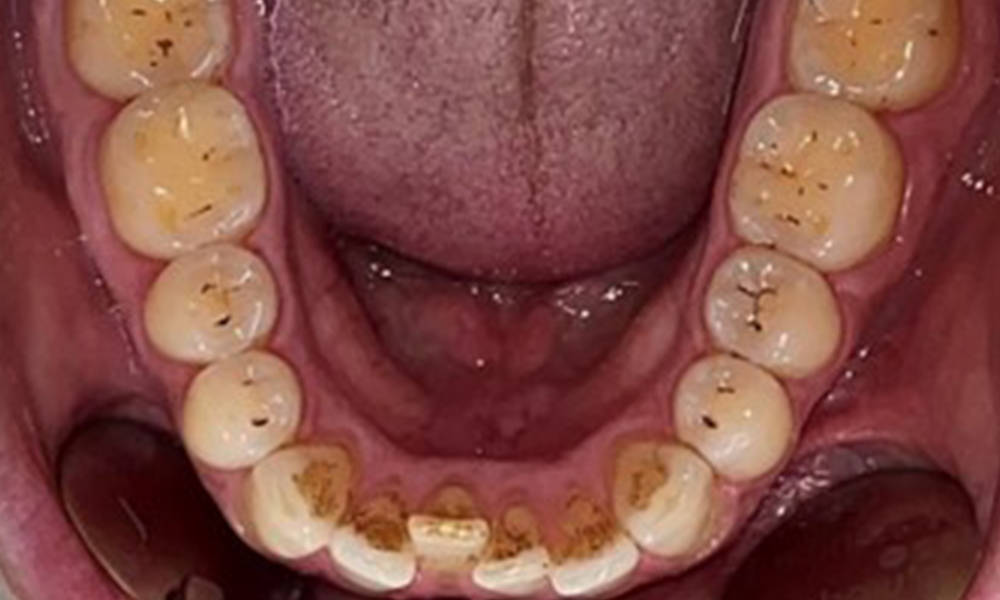

Occlusal view of the mandible.

Fig. 4: Occlusal view of the mandible, © Dr R. Krapf

Dental findings

The patient has full dentition with a total of 28 teeth. There were noteworthy erosions and attritions. (Fig. 4, Fig. 5). Due to bruxism, the patient has been wearing a splint with an adjusted bite block at night for many years. The erosions were caused by long-term consumption of isotonic beverages. No periodontal bone loss or active caries were observed.